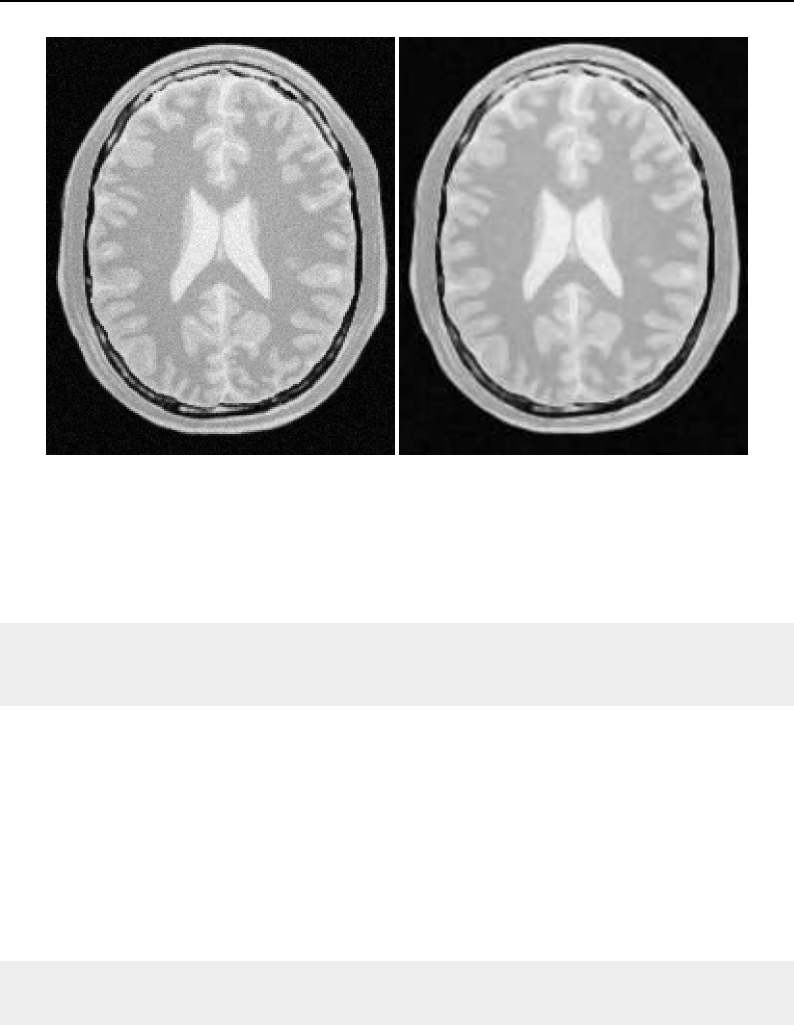

The National Library of Medicine Insight Segmentation and Registration Toolkit, shortened as the

Insight Toolkit (ITK), is an open-source software toolkit for performing registration and segmenta-

tion. Segmentation is the process of identifying and classifying data found in a digitally sampled

representation. Typically the sampled representation is an image acquired from such medical instru-

mentation as CT or MRI scanners. Registration is the task of aligning or developing correspondences

between data. For example, in the medical environment, a CT scan may be aligned with a MRI scan

in order to combine the information contained in both.